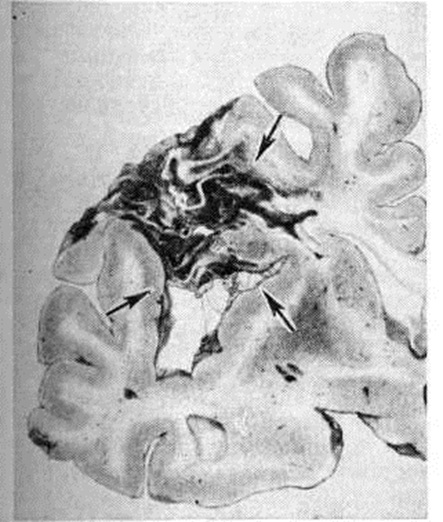

Кровоизлияния типа гематомы сопровождаются образованием полости, содержащей жидкую кровь или свёртки крови; они составляют 85% внутримозговых кровоизлияний, наиболее часто развиваются в подкорковых узлах, реже в мозжечке. Основной механизм развития гематомы — разрыв патологически изменённого сосуда (рисунок 7). Формирование гематомы идёт путём раздвигания кровью вещества мозга с перемещением его участков, что возможно благодаря резервным пространствам (желудочки, подпаутинное пространство). Размеры гематомы при этом превышают объем разрушенного кровью вещества, сдавление окружающих отделов незначительно; лишь при кровоизлиянии в мозжечок сдавление вещества мозга весьма существенно в связи с анатомическими особенностями задней черепной ямки (рисунок 8).

Рис. 8.

Фронтальный срез мозжечка и продолговатого мозга с кров излиянием в мозжечок (гематома указана стрелкой).